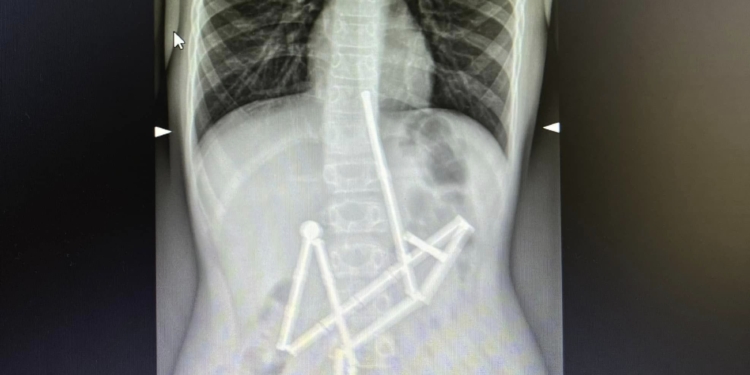

Вже на першому рентген-знімку спеціалісти побачили наявність у травному каналі цілої групи сторонніх тіл, у яких вдалось впізнати магнітний конструктор. 20 магнітів знаходились у різних частинах шлунково-кишкового тракту, проте були зʼєднані між собою.

Консиліумом лікарів було прийняте рішення про проведення невідкладного оперативного втручання, адже кожна година очікування могла погіршити стан пацієнта. Відмінність магнітів від інших сторонніх тіл, які можуть проковтнути діти, полягає у їх притягненні один до одного та защемленні тканин. Як наслідок, виникають зони некрозу (змертвіння), перфорації порожнистих органів, шлунково-кишкові непрохідності тощо.

Бригада анестезіологів якнайшвидше ініціювала передопераційну підготовку та введення в наркоз. Першою до роботи долучилась команда спеціалістів відділення ендоскопії. Вони провели дослідження слизових оболонок стравоходу, шлунку та дванадцятипалої кишки (езофагогастродуоденоскопія) та оцінили стан верхніх відділів травного тракту, виявили проковтнуті обʼєкти, що були зчеплені між собою. Медикам вдалося захопити перший магніт і витягти його разом із ланцюжком з 18 елементів конструктора.

Проте один магніт залишився, й спеціалісти не мали змоги видалити його ендоскопічно. Надалі за операційним столом почали працювати хірурги. Була виконана лапаротомія та ретельна ревізія органів черевної порожнини. Під час цього в дитини було виявлено 5 перфоративних отворів та останній елемент конструктора. Всі отвори були закрито, а магніт видалено.